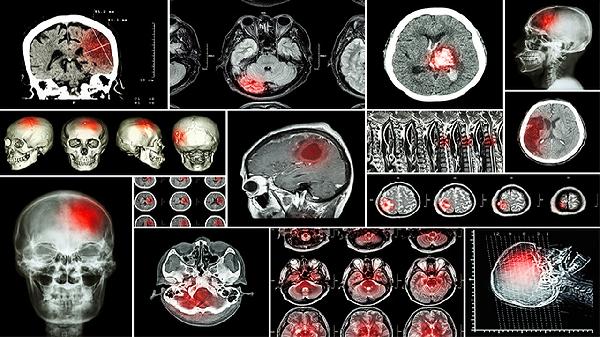

孩子小脑损伤的症状有哪些

孩子小脑损伤的症状主要有共济失调、肌张力低下、眼球震颤、语言障碍和平衡障碍。小脑损伤可能由先天性发育异常、围产期缺氧、外伤、感染或肿瘤等因素引起,需结合影像学检查确诊。